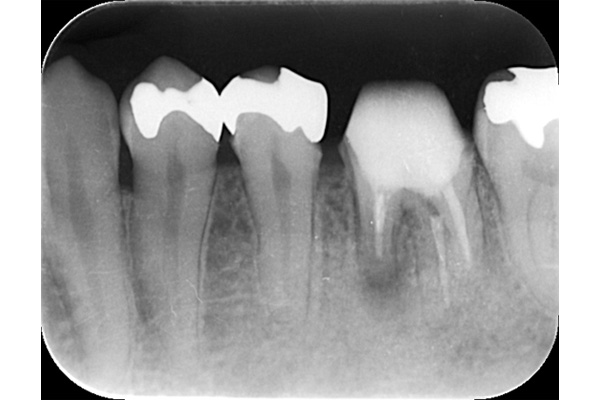

左のレントゲンでは破折したかどうかはわからないが、虫歯になっている部分をとっていくと歯が割れているのがはっきりとわかりました。

歯が割れるケースで多いのが金属の土台(メタルコア)が入っている場合です。特に根の中に長いものが入っていると、歯を割る力が強くかかるため、割れることが多いです。